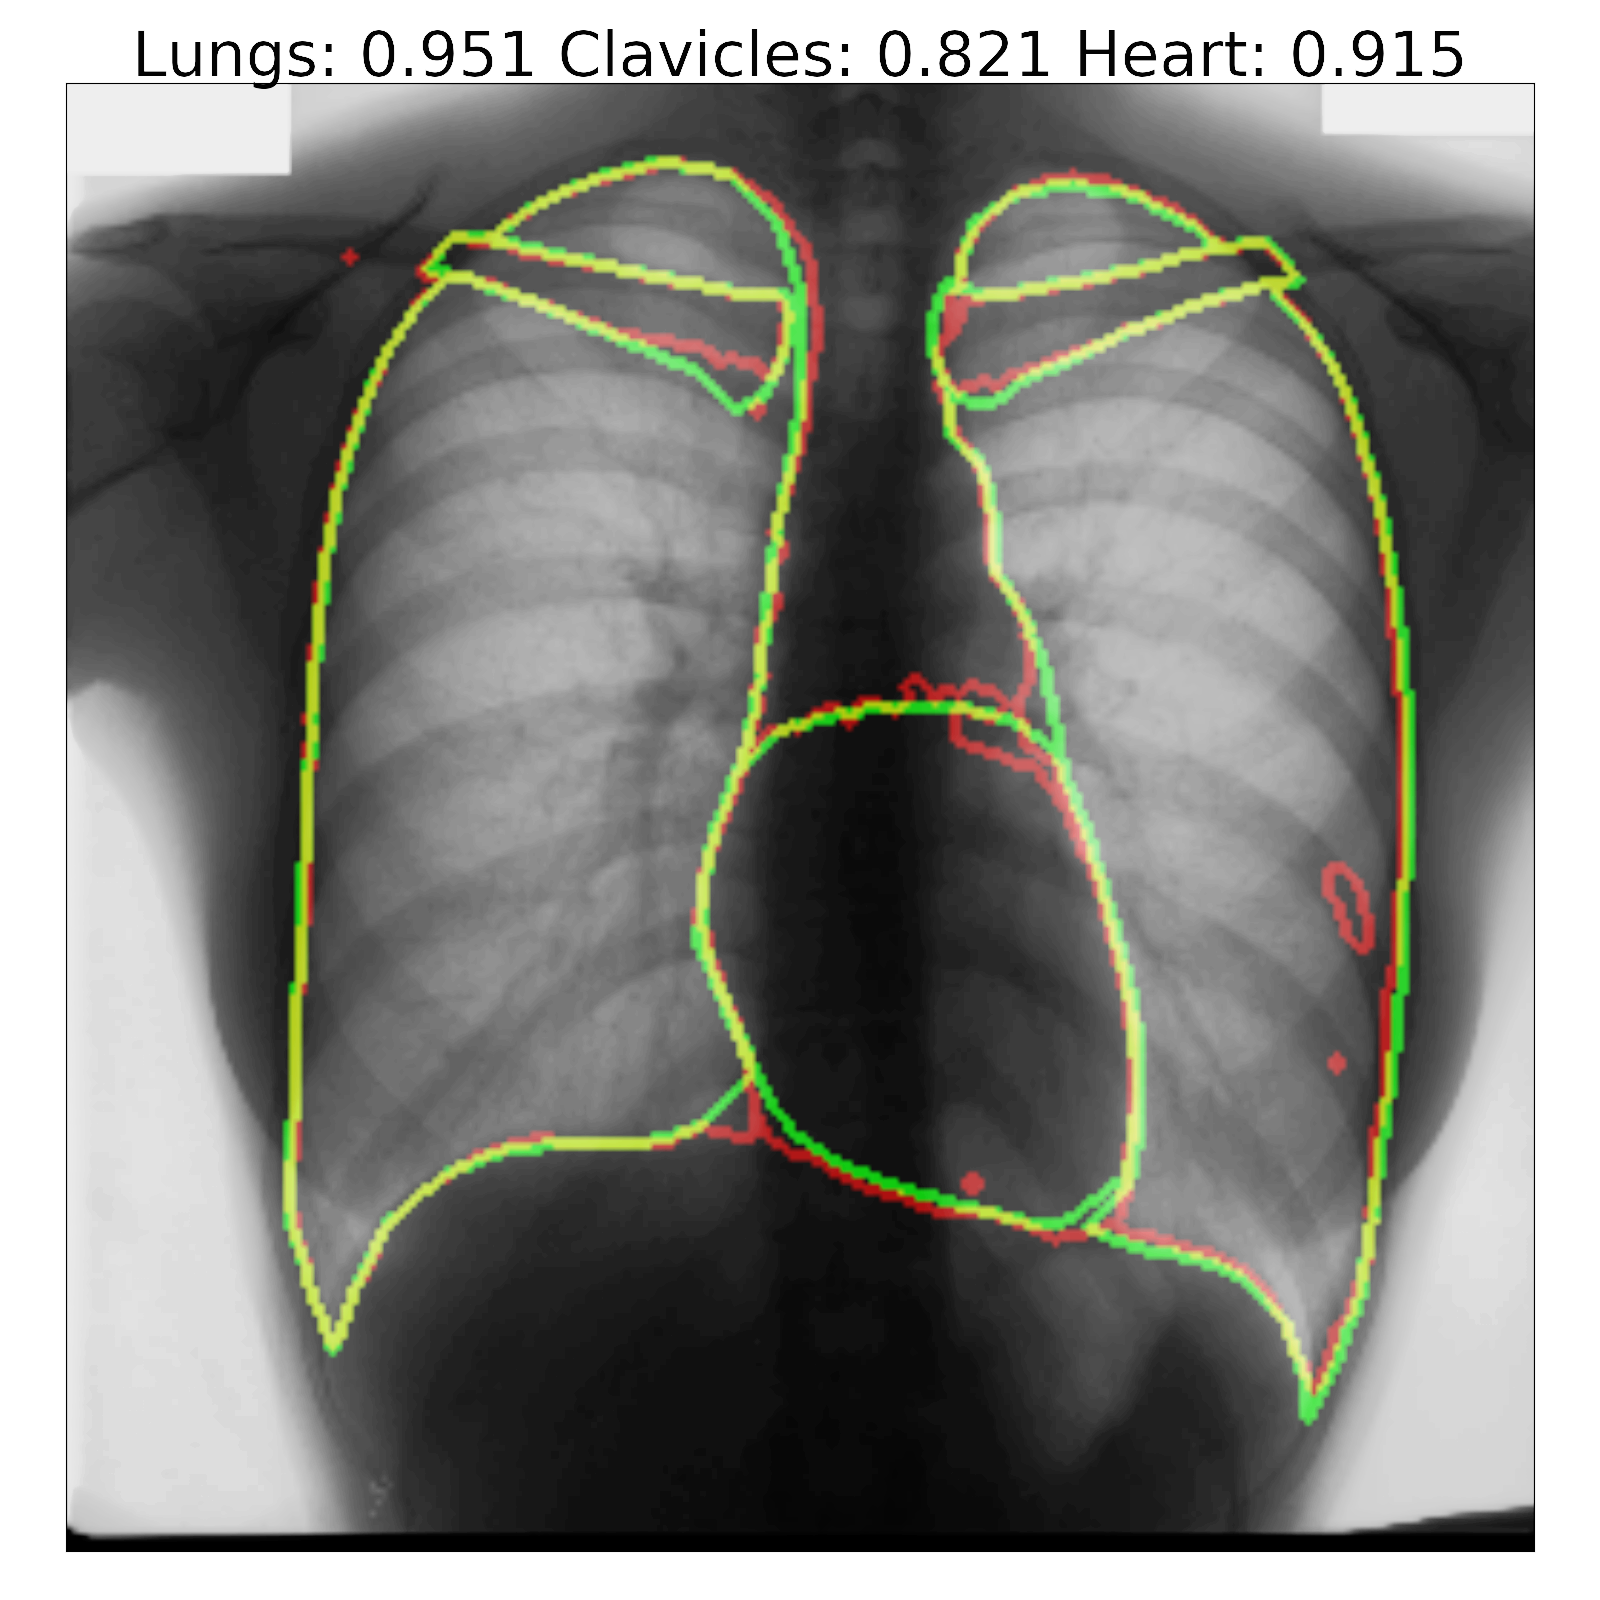

Figure 7: Segmentation results and corresponding Jaccard scores on some images for U-Net (top row) and proposed InvertedNet with ELUs (bottom row). The contour of the ground-truth is shown in green, segmentation result of the algorithm in red and overlap of two contours in yellow.

Fig. 7 shows a few examples of the algorithm results for both successful and failed cases for U-Net (top) and the InvertedNet  trained with the ELU and loss function based on the Dice coefficient. The white boxes show Jaccard scores for lungs, clavicles and heart. To extract the shape contours of the segmentation and ground-truth, we used a morphological outline extraction algorithm on both segmentation result and reference masks. The contour of the ground-truth is shown in green, the segmentation result of the algorithm in red and the overlap of two contours in yellow colors.